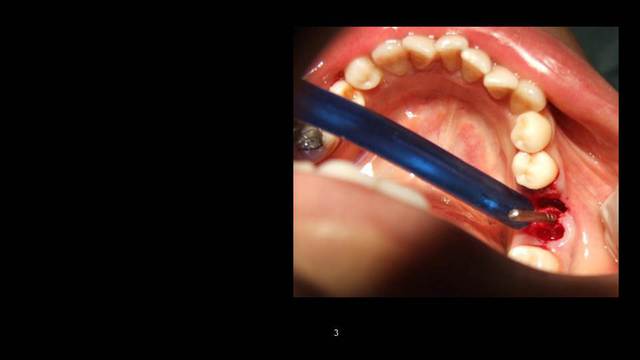

Cookie Consent byPrivacyPolicies.comInsertion immediate au niveau de 46 dans le septum - Eugenol

Insertion immediate au niveau de 46 dans le septum